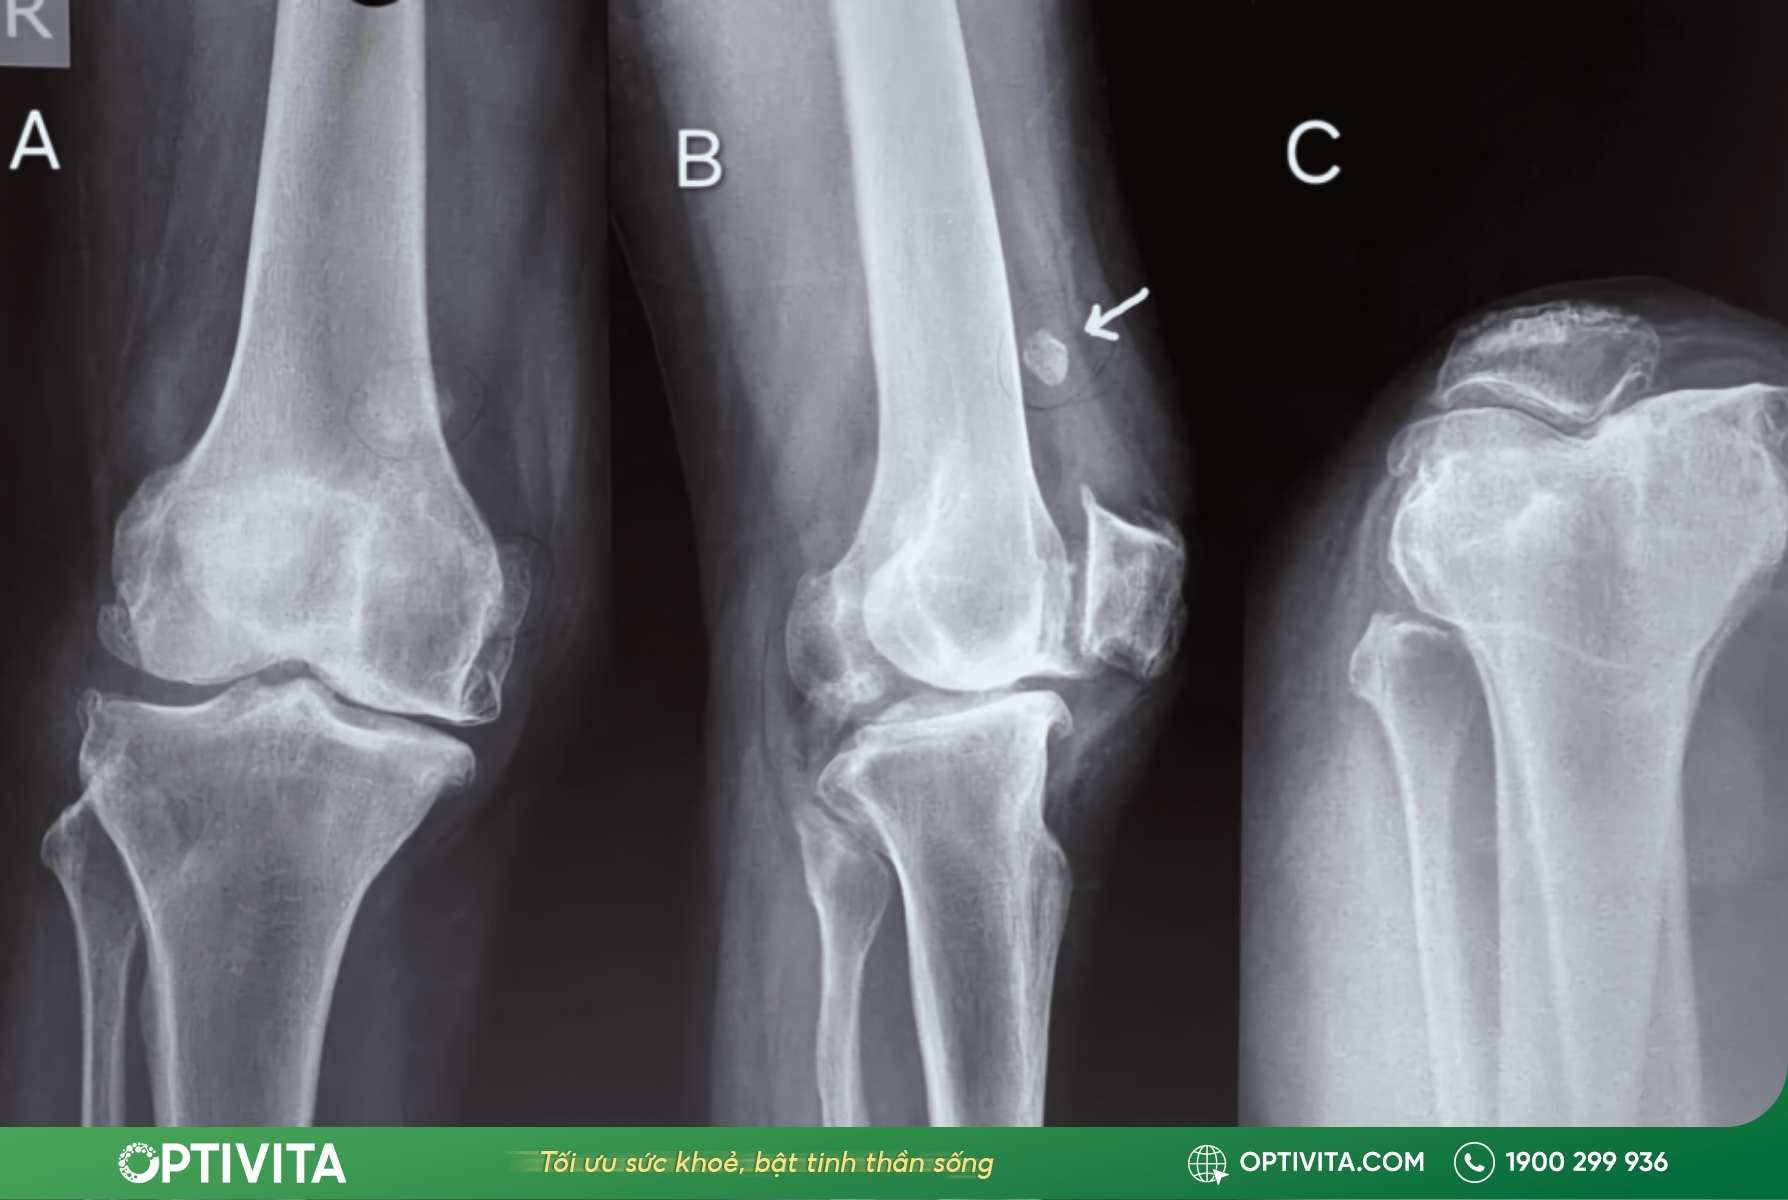

Vai trò của X-quang và MRI trong chẩn đoán xác định

Bác sĩ không thể chỉ nhìn bằng mắt thường để kết luận bệnh. Hai phương pháp chẩn đoán hình ảnh dưới đây là bắt buộc:

- X-quang (Chụp phim thường quy): Hình ảnh X-quang cho phép bác sĩ quan sát rõ vị trí, số lượng và hình thái của khối u (có cuống hay không có cuống). Quan trọng hơn, nó giúp phân biệt sơ bộ u xương sụn với các tổn thương xương khác như gãy xương cũ hay gai xương thoái hóa.

- MRI (Cộng hưởng từ): Nếu X-quang chỉ thấy được phần xương, thì MRI cho phép nhìn thấu cấu trúc mô mềm, đặc biệt là đo chính xác độ dày của mũ sụn. Như đã đề cập, nếu lớp mũ sụn này dày bất thường (trên 2cm ở người lớn), đây là tín hiệu cảnh báo nguy cơ ác tính cần sinh thiết ngay lập tức.